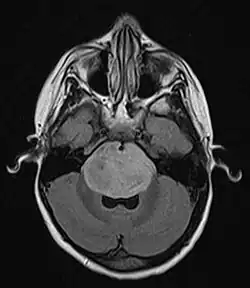

Brain stem glioma. MRI axial, with contrast

Neuroimaging, such as MRI, is the main diagnostic tool for brain stem gliomas. In very rare cases, surgery and biopsy are performed.